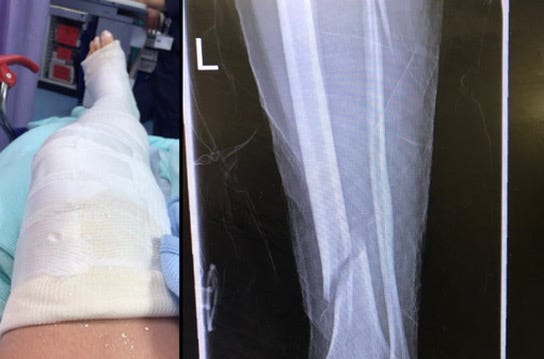

It was our daughters birthday, and I was organising a roller skate party on the skate ramp we had recently installed in our workshop. I had spent two weeks painting a mural especially and was super tired. I had set the whole space up with balloons and lights and music. It was lockdown so the only people at this party would be our family. Just before the girls were due to arrive I put my skates on and had a little roll around on the ramp. I had a moment where I nearly fell but I caught myself. I suddenly had a very piercing thought. What if I break my leg and ruin Bea’s birthday party? Now this was an unusual thought for me because firstly, I was falling over fairly often as I whole heartedly flung myself into becoming a better skater and it didn’t bother me. Mostly I could catch myself, and seldom damaged myself when I did fall. I just sort of bounce instead. Secondly, my main fear if I am to break myself is that I would break my wrists as these I need for my work. Leg? That thought had never occurred to me before so when it came to me this time, I noticed it. It was out of the ordinary. But I discarded it with another thought: ‘Don’t be silly, you’ll be fine’. Ten minutes later the girls arrived. Ten minutes or so after that I was showing off for them and I went to spin and my body went round but my skates locked on something and I fell, and sat on my own leg snapping my bones into six pieces. Some of the breaks were at the bottom just above my ankle and one of the breaks was right below my left knee. As I lay there waiting for the ambulance to arrive the thought that went round in my head was ‘It happened!’ It actually happened?!?!? I saw it coming, and it happened! How weird is that??

Months prior to this very life altering incident, I had a dream that I was at the workshop and I cut my left leg off just below the knee… so that piercing thought was not my only warning!!!

Recovery from this injury has been rediculously long, in the region of four years, having needed to have a titanium plate and three surgeries to correct it. So I have had plenty of time to consider what happened. In the months that followed I read everything I could about intuition and precognition. I wanted to make sure that I honed that skill and if I ever have warnings again, that I see them for what they are and endeavour to adjust. I have had several warnings since and have altered my behaviour everytime. The problem with that is you can only say you were right about a precognition if the evert actually occurs. If you manage to avoid it, well there is no proof. But you and I know, after collecting the crazy weird coincidences in these Glitch Logs that the intuitive warnings are worth listening to, and I’d rather not have an incident for my Glitch Log than another life altering event that could have been avoided!